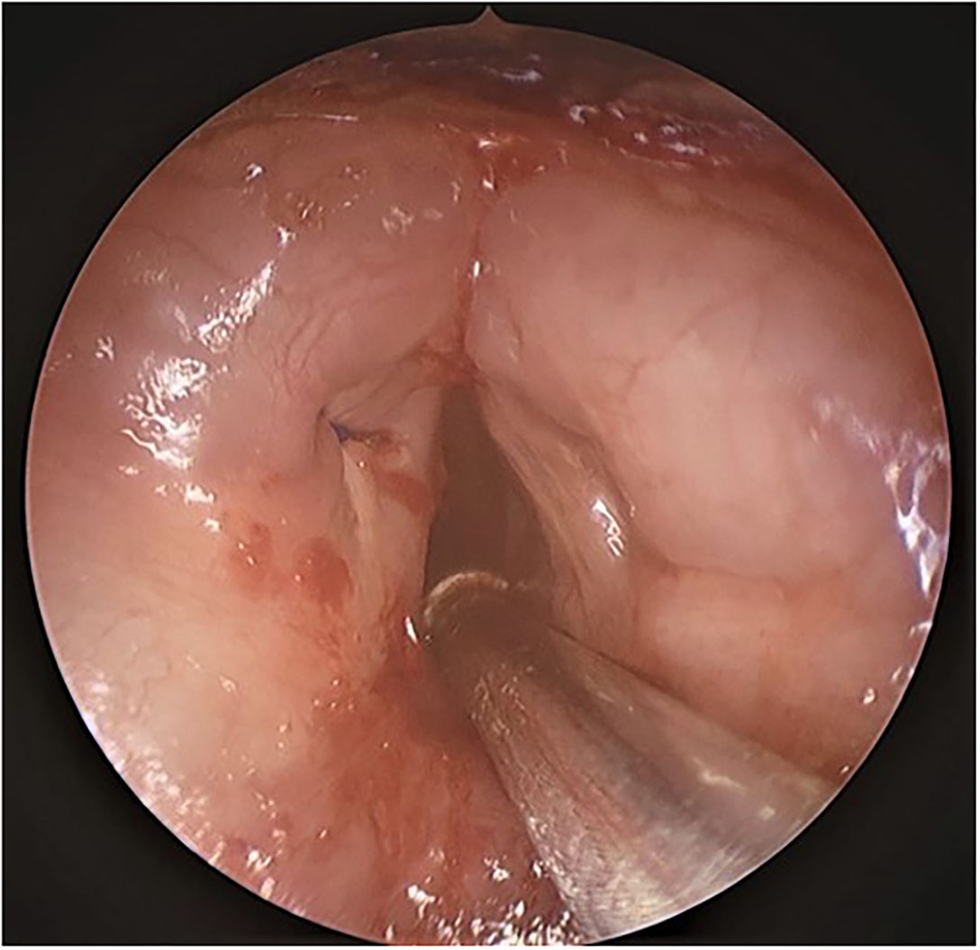

The present surgical technique is described in a 15-month-old otherwise healthy child with Type 2 Laryngeal web (Figure 1) who presented with a weak voice. The case was retrospectively reviewed under University of Iowa IRB No: 20210205.

Figure 1

Endoscopic view of Type 2 laryngeal web.